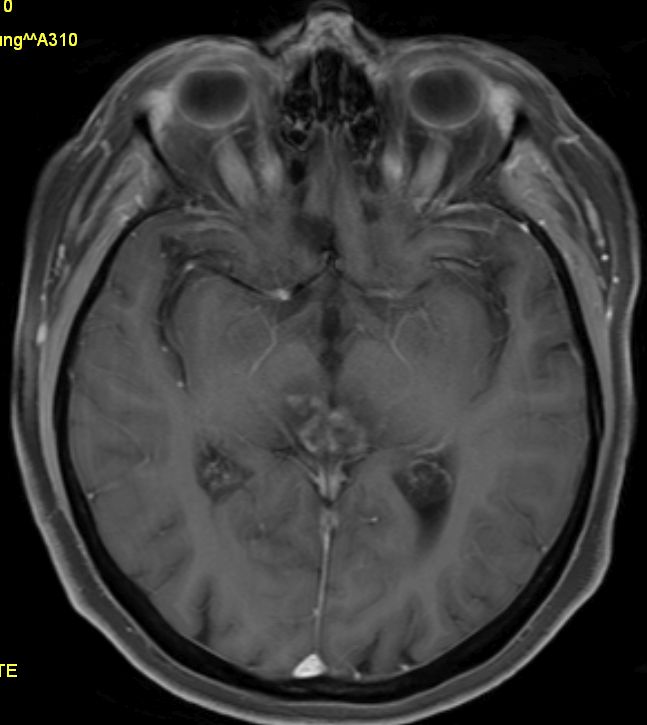

Vierhügelplatte 66-jährige Frau mit Sehstörungen, Ptose rechts mehr als links, Gehörverschlechterung und Gleichgewichtsstörungen. Stereotaktische Biopsie: Astrozytom Grad 3 (Grad unsicher).